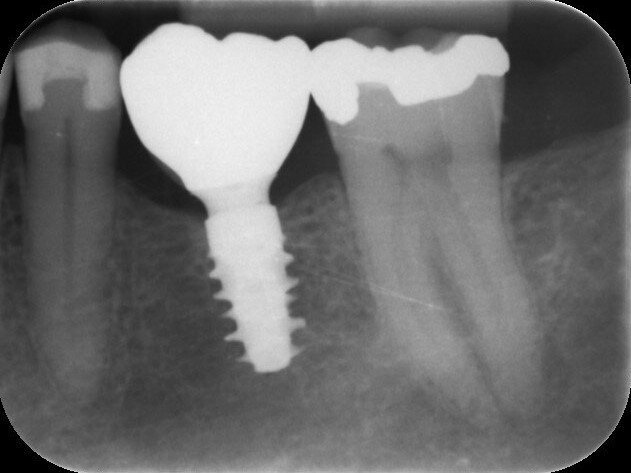

Fig. 6: Radiograph confirming the seating of a healing abutment of 6.5 mm in diameter and 1.5 mm in gingival height.

Fig. 12: Radiograph confirming the correct seating of the temporary crown—no gap visible.

Fig. 19: Radiograph confirming the correct seating of the final crown—no gap visible.

Fig. 22: One-year follow-up radiograph.

The patient, a 67-year-old non-smoking man without any relevant medical history, was referred to the office with a missing tooth (#36) due to persistent apical periodontitis. The tooth had been extracted more than one year prior to the procedure and the molar site was well maintained and fully healed (Fig. 1). A CBCT scan showed that the patient had favourable bone availability (Fig. 2), on which basis a one-stage placement of a 5.5 × 10.0 mm Straumann BLX implant was planned. After surgically installing the implant (Figs. 3–7), Salvesen allowed the surrounding soft tissue to mature and heal for six weeks (Fig. 8). He then removed the healing abutment to begin the prosthetic procedures for a temporary crown (Figs. 9 & 10). A stone master cast was made in the laboratory, and a temporary screw-retained PMMA crown was manufactured over a Straumann wide base temporary abutment for the crown (Fig. 11) and placed on to the implant (Figs. 12–14).

One year after the treatment, the patient reports complete satisfaction with both his chewing function and the overall aesthetics (Figs. 20 & 21). Radiographs confirm that the molar site is stable and healthy (Fig. 22). In this first human case, use of the Straumann BLX wide base implant delivered efficient and reliable performance, even in soft bone with early loading conditions.